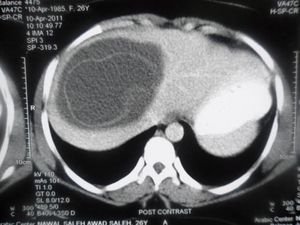

Hydatid Liver cyst

Stade 2 of Garbi classification.